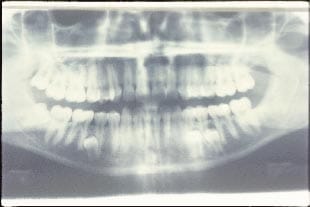

Kiểm tra bằng chụp X-quang

Khi có dấu hiệu bất thường trong lâm sàng thì cần phải chỉ định kiểm tra bằng x-quang. Tùy từng trường hợp cụ thể mà bác sĩ có thể chỉ định chụp X-quang hoặc phim quanh chóp, phim toàn cảnh để nhìn thấy được hình ảnh chi tiết răng cửa. Nội soi răng miệng có thể cung cấp cho dấu vết sai lệch chiều sâu của răng.